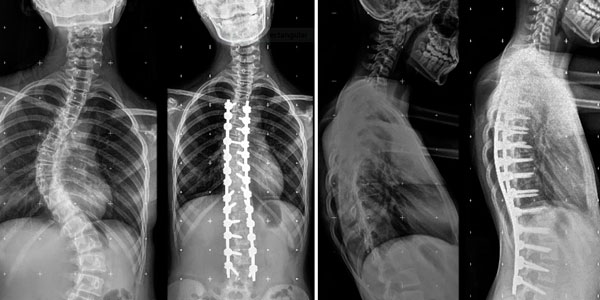

Mi mama y Yo comenzamos a notar que mi columna estaba torcida, consultamos varias clínicas y sinceramente el único que nos explico con detalle mi enfermedad fue el Dr. Carlos Cardenas, pareciera que otro médicos no conocían esta enfermedad. Mi diagnostico fue escoliosis idiopática del adolescente.

El único tratamiento para mi caso es con cirugía, tenia mucho miedo y me costo mucho decidir operarme.

Actualmente tengo 8 anos operada, y hago mi vida normal, hasta hago deporte, no tengo restricciones para nada.